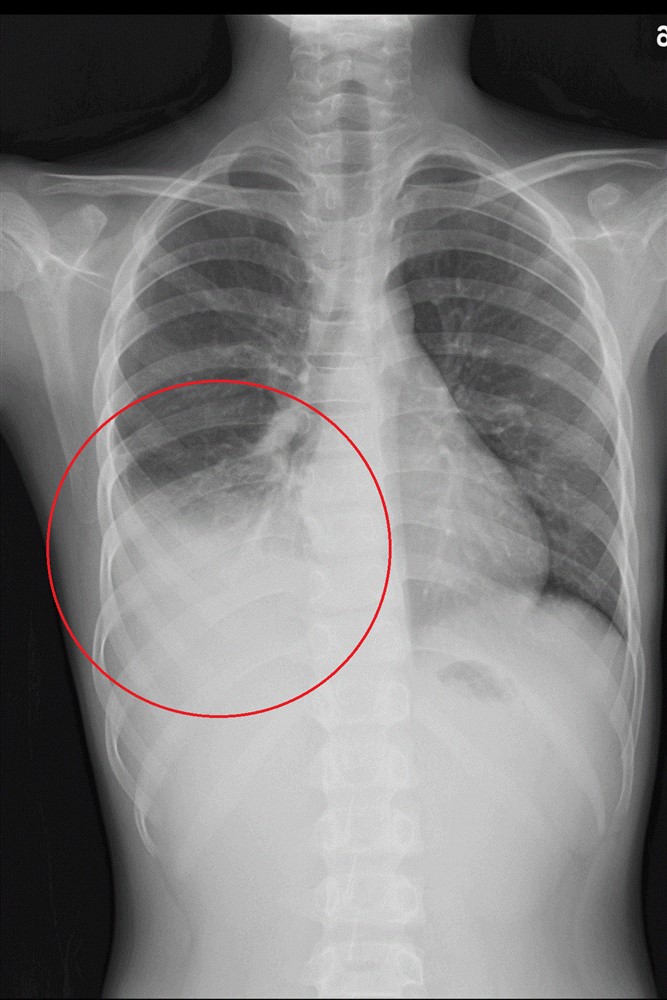

經抗生素治療後高燒未退甚至出現肺炎擴散及肋膜積水的情形(上圖);先後使用口服四環黴素及喹諾酮類藥物進行治療,肺部積水明顯減少(下圖)。圖/台北慈院提供

經診斷為社區性肺炎,因黴漿菌急性抗體呈現陽性,懷疑為肺炎黴漿菌感染,考量情況較為嚴重,由小兒科醫師收治住院觀察。但病情萬變,經抗生素治療後許小弟仍然高燒未退甚至出現肺炎擴散及肋膜積水的情形,遂照會小兒感染科吳秉昇醫師,透過黴漿菌抗生素的調整,當晚許小弟即逐漸退燒,一週後平安出院,後續胸部X 光追蹤亦發現右下肺炎及肋膜積水已改善。

黴漿菌肺炎以抗生素治療為主,過往多半使用紅黴素,但衛福部疾管署《感染控制雜誌》研究曾指出,臺灣兒童感染的黴漿菌已對紅黴素產生六成以上的抗藥性,必要時須改以其他抗生素,如四環黴素或喹諾酮類抗生素治療。以許小弟為例,醫療團隊評估其症狀較為嚴重,且之前曾使用紅黴素治療,可能有紅黴素抗藥的情形,因此先後使用口服四環黴素及喹諾酮類藥物進行治療,發燒才逐漸改善,四天後肺部積水也明顯減少,病況穩定。吳秉昇醫師表示:「醫師開立抗生素藥物會考量其年齡與臨床症狀嚴重度,並參考醫療指引進行治療,因此家長應遵從醫囑,按處方開立的劑量與時間讓孩童服用。」